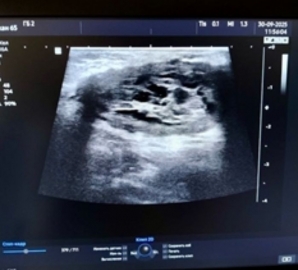

Региональный минздрав сообщает, что в конце сентября в Ульяновске городская больница №2 получила современный ультразвуковой аппарат отечественного производства — РуСкан 65. Оборудование уже активно используется специалистами.

Новый аппарат экспертного класса позволяет проводить широкий спектр исследований: сердечно-сосудистой, пищеварительной, эндокринной и половой систем, плевральных полостей, а также мягких тканей.

Благодаря функции подавления шумов устройство обеспечивает высокую чёткость изображения, что повышает точность диагностики и помогает своевременно выявлять онкопатологию. У аппарата лёгкие эргономичные монокристальные датчики, сенсорный дисплей и увеличенный экран с высоким разрешением, что снижает нагрузку на глаза. На панели управления расположены крупные кнопки с мягкой подсветкой, позволяющие не отвлекаться на настройку, а сосредоточиться на исследовании.